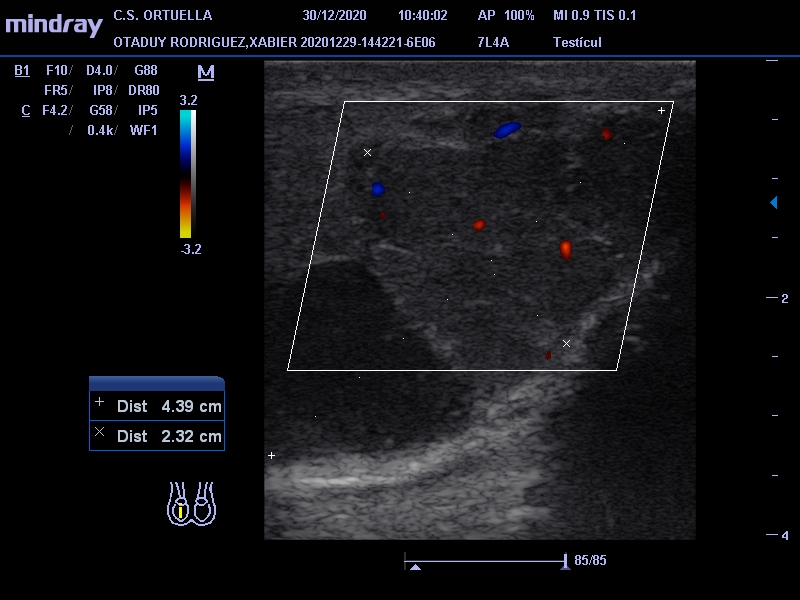

Hallazgos ecográficos

Masa de 38 x 40 mm, hipoecogénica, con aumento de vascularización mediante doppler, en polo inferior de teste derecho.